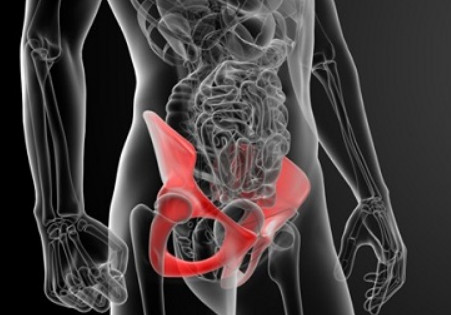

고관절 통증은 고관절과 관련된 관절 통증으로 정의됩니다. 이 관절은 상체에서 체중을 분산시키는 역할을 담당하며, 걷거나 뛸 때에는 체중의 약 3배나 10배가량의 부하를 견딥니다. 다른 관절과 마찬가지로 충격이나 체중 변화가 고관절 통증 증상을 유발할 수 있습니다. 이러한 통증 증상을 일으키는 주요 질환으로는 퇴행성 고관절염, 대퇴골 골절 그리고 선천성 고관절 탈구 등이 있습니다.

고관절은 골반과 대퇴골의 대퇴골두가 만나는 관절로, 상체와 하체를 연결하는 중요한 부위입니다. 이 관절은 서 있거나 앉아 있을 때부터 평소 일상생활에서 빈번하게 활용되는데, 이로 인해 상당한 부담을 견뎌내야 합니다. 고관절은 탁구공과 비슷한 크기와 모양을 가진 대퇴골두가 지탱하는데, 걸을 때 고관절에 가해지는 무게는 체중의 3~4.5배까지 증가하며 만약 계단을 오를 때는 대퇴골두가 체중의 8배에 달하는 부담을 견뎌야 하므로, 고관절은 상당한 스트레스와 손상의 위험에 노출될 수 있습니다.